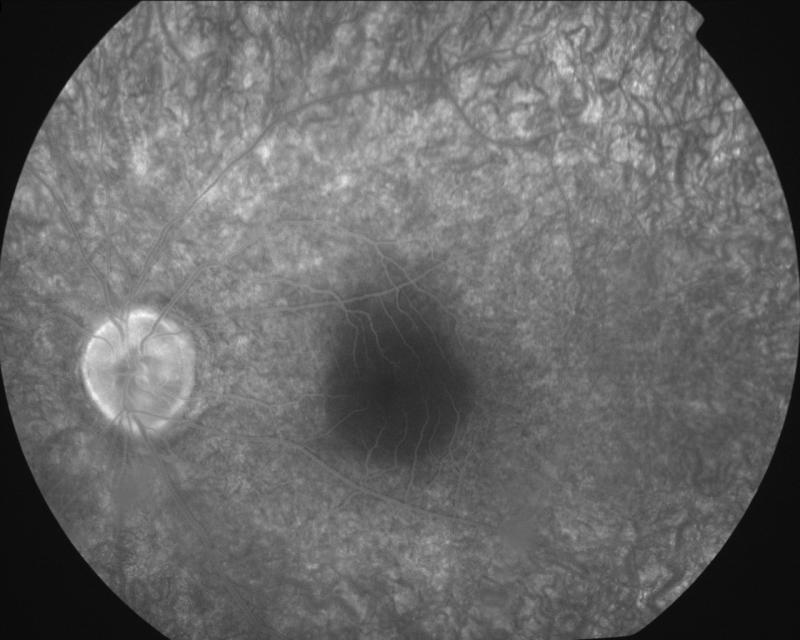

2004032205\22-03-2004

IM000035.JPG